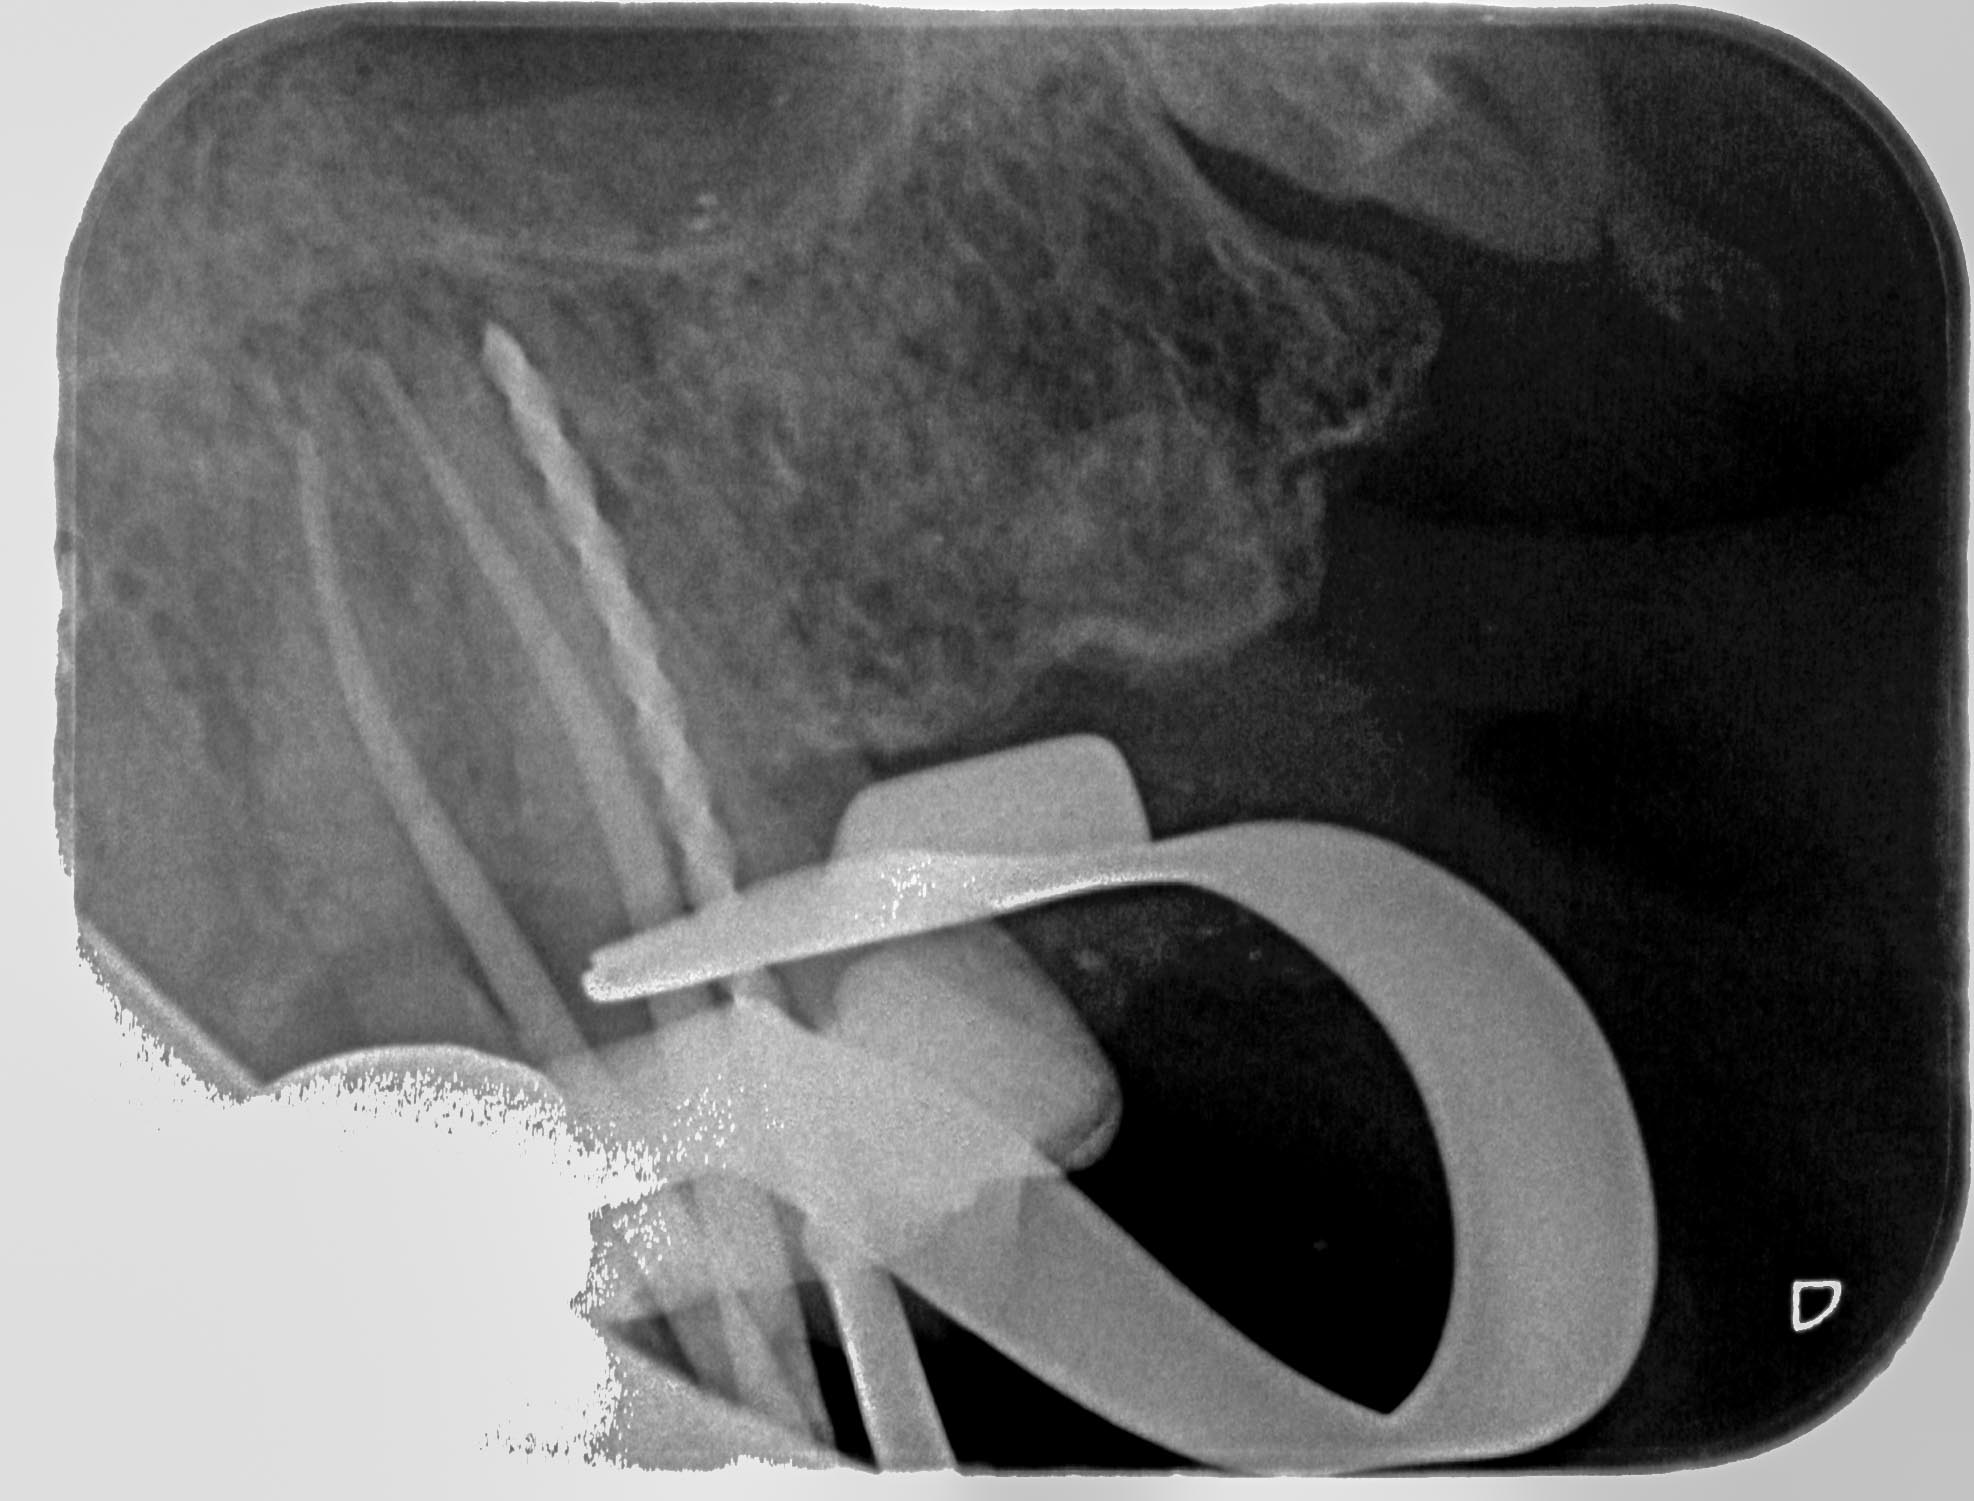

KC27-1-3 Veröffentlicht 25. Juni 2015 am 1974 × 1501 in Zahn 27- Interne Resorption, apikale Aufhellung